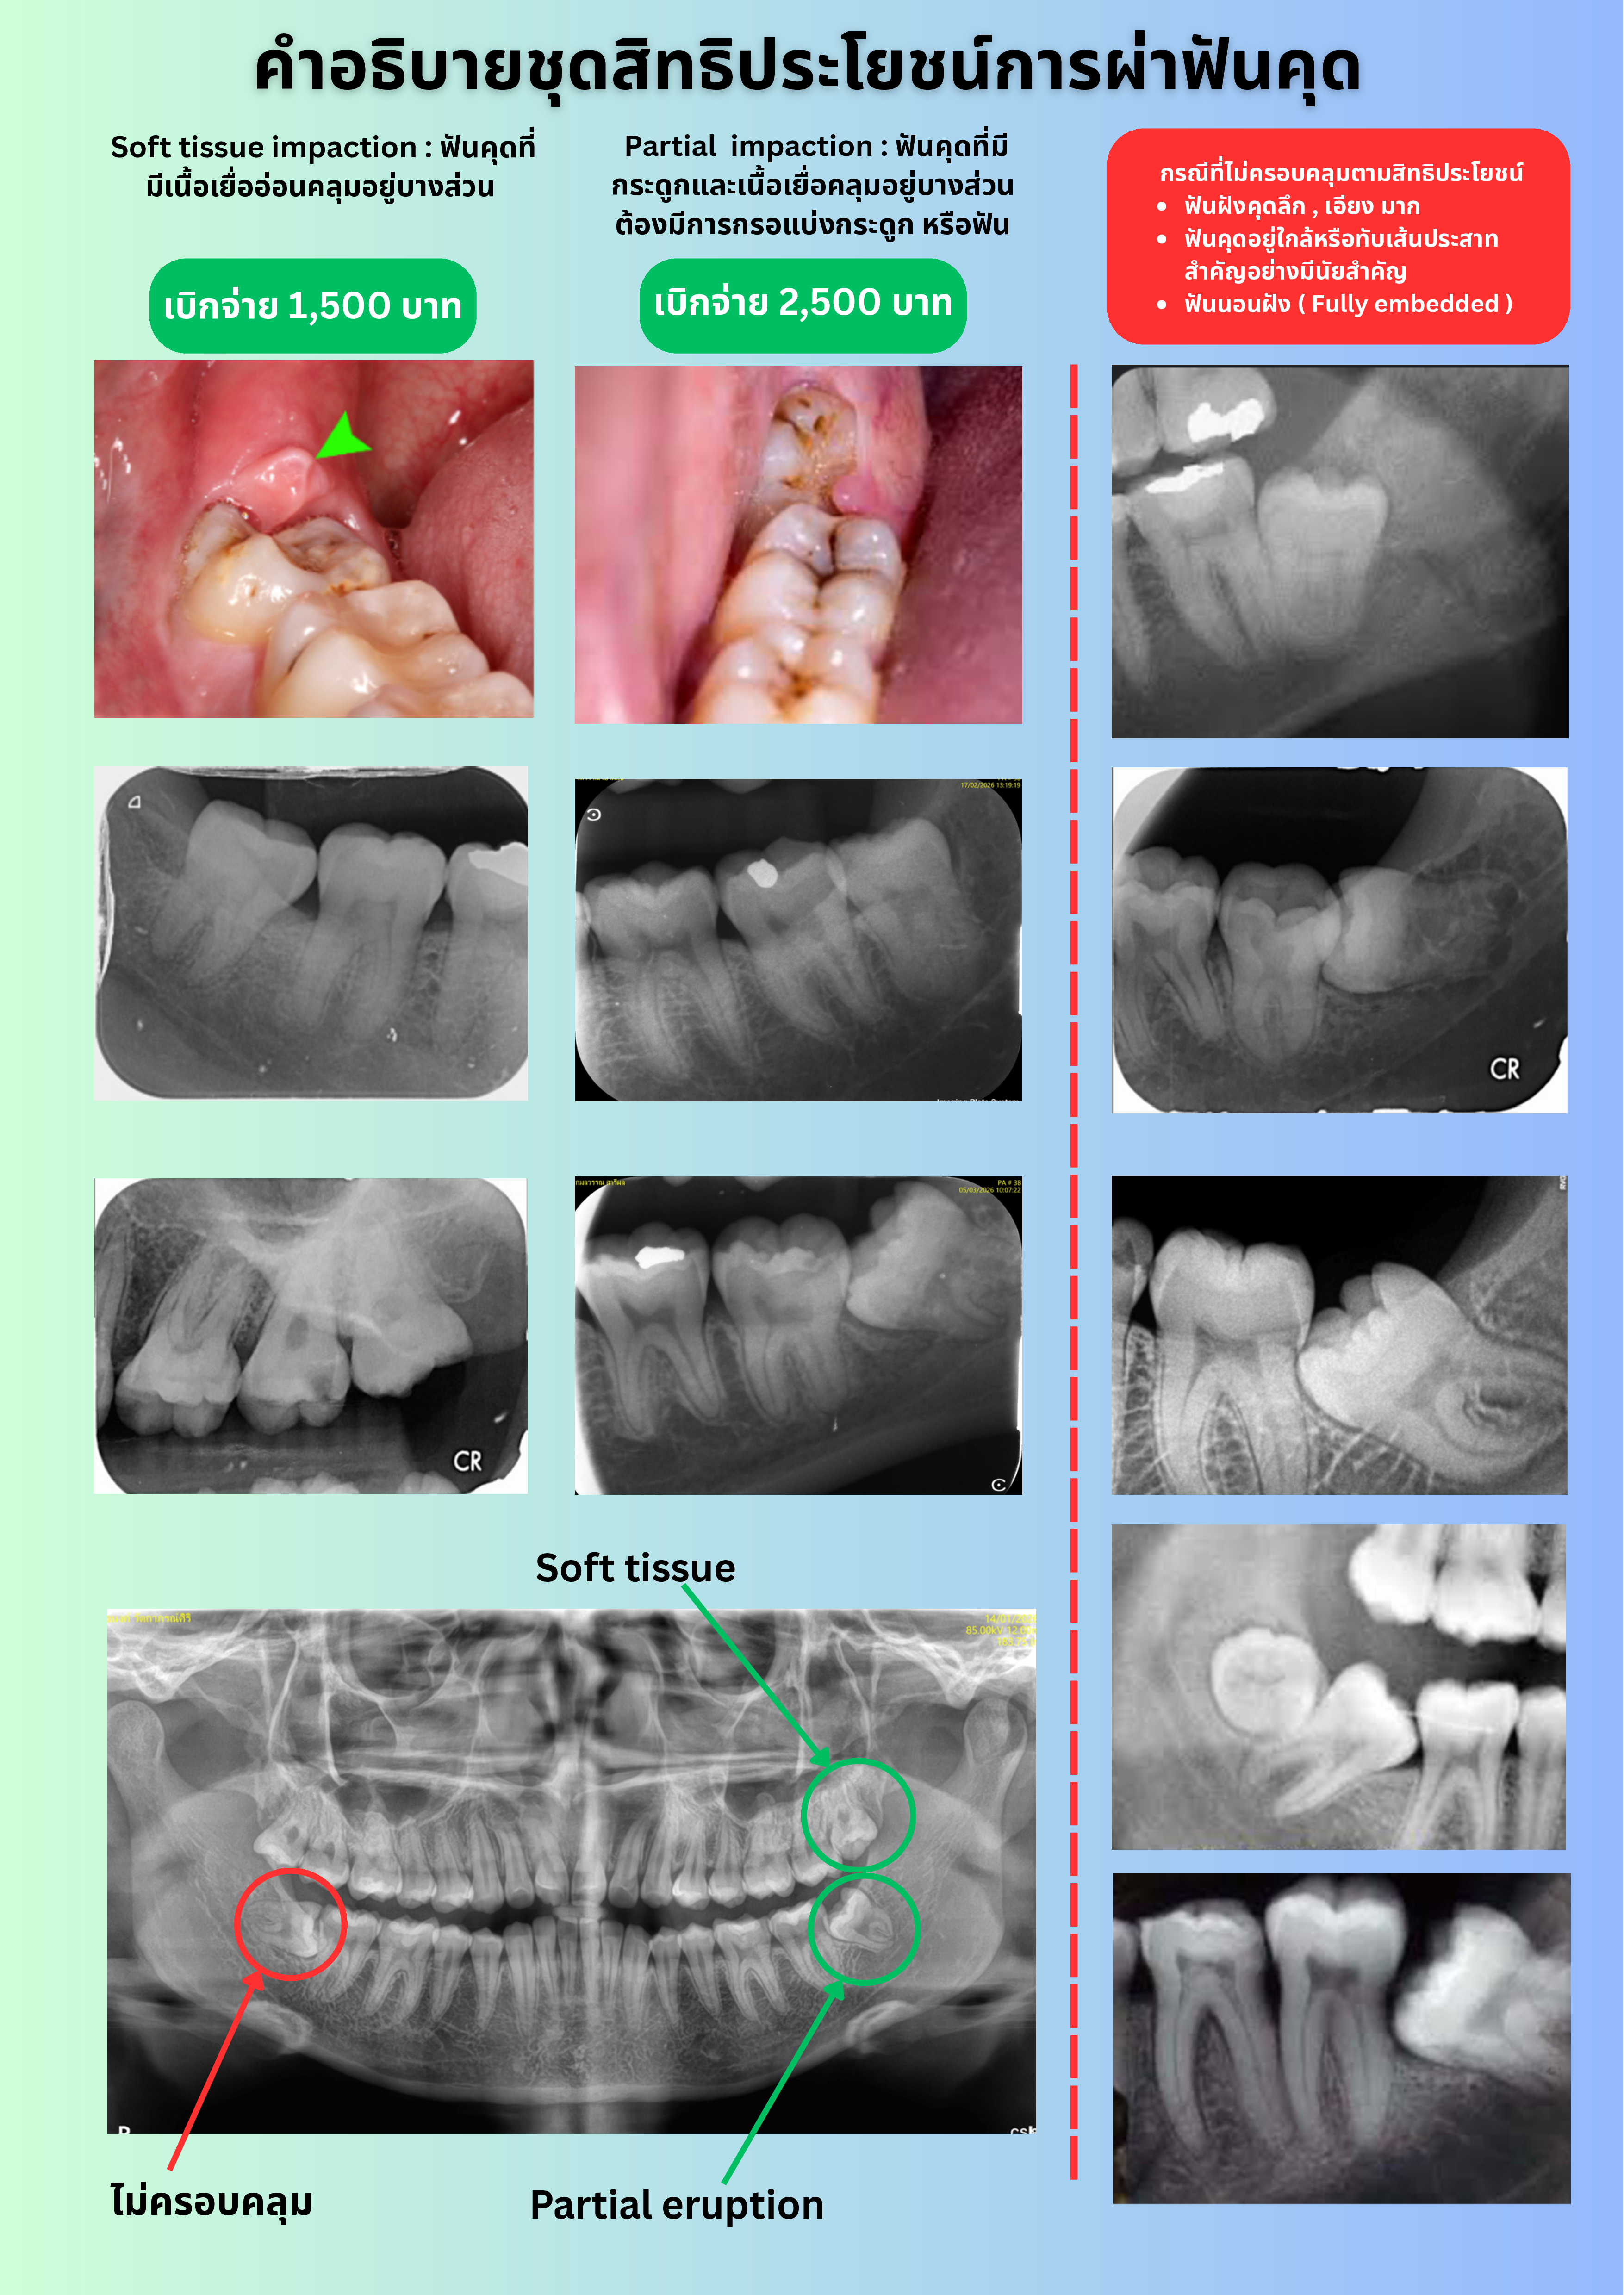

สำหรับฟันคุดที่อยู่ในกระดูกบางส่วน (Partial Bony Impaction Tooth) ที่ทันตแพทยสภาเสนอต่อสำนักงานประกันสังคม จะเป็นกรณีเฉพาะที่ไม่ซับซ้อน มีระดับความยากที่เหมาะสมกับการให้บริการของคลินิกทันตกรรมเอกชนโดยทั่วไป ซึ่งทันตแพทยสภาได้เคยให้ข้อเสนอแนะต่อสำนักงานประกันสังคม ว่าควรมีภาพฟันคุดประกาศอย่างเป็นทางการ เพื่ออธิบายว่าลักษณะฟันคุดและภาพถ่ายรังสีฟันคุดแบบใด ที่ครอบคลุมสิทธิประโยชน์ และแบบใดที่อยู่นอกเหนือสิทธิประโยชน์ เพื่อให้เกิดความเข้าใจกันในการสื่อสารระหว่างสถานพยาบาลและผู้ประกันตน

สำหรับสิทธิประโยชน์ผ่าฟันคุดของประกันสังคม จะครอบคลุมเฉพาะ ฟันคุดที่ขึ้นไม่ได้เนื่องจากมีเนื้อเยื่ออ่อนคลุมอยู่บางส่วน (Soft Tissue Impaction Tooth) และฟันคุดที่อยู่ในกระดูกบางส่วน (Partial Bony Impaction Tooth) เท่านั้น ฟันคุดที่มีกระดูกคลุมอยู่ทั้งซี่ (Completed Bony Impaction Tooth) จะไม่อยู่ในสิทธิประโยชน์ที่ประกันสังคมกำหนดไว้ ดังนั้นหากผู้ประกันตนจะรักษาในสถานพยาบาลคลินิกทันตกรรมเอกชน ผู้ป่วยจะต้องเป็นผู้จ่ายค่ารักษาด้วยตนเองทั้งหมด ไม่สามารถเบิกกับประกันสังคมได้ สำหรับทางเลือกในการรักษาฟันคุดที่อยู่ในกระดูกบางส่วนที่มีความซับซ้อน ฟันคุดที่มีกระดูกคลุมอยู่ทั้งซี่ ผู้ประกันตนสามารถเข้ารับบริการในโรงพยาบาลของรัฐที่ทำ MOU กับทางประกันสังคมได้โดยไม่เสียค่าใช้จ่ายใด ๆ